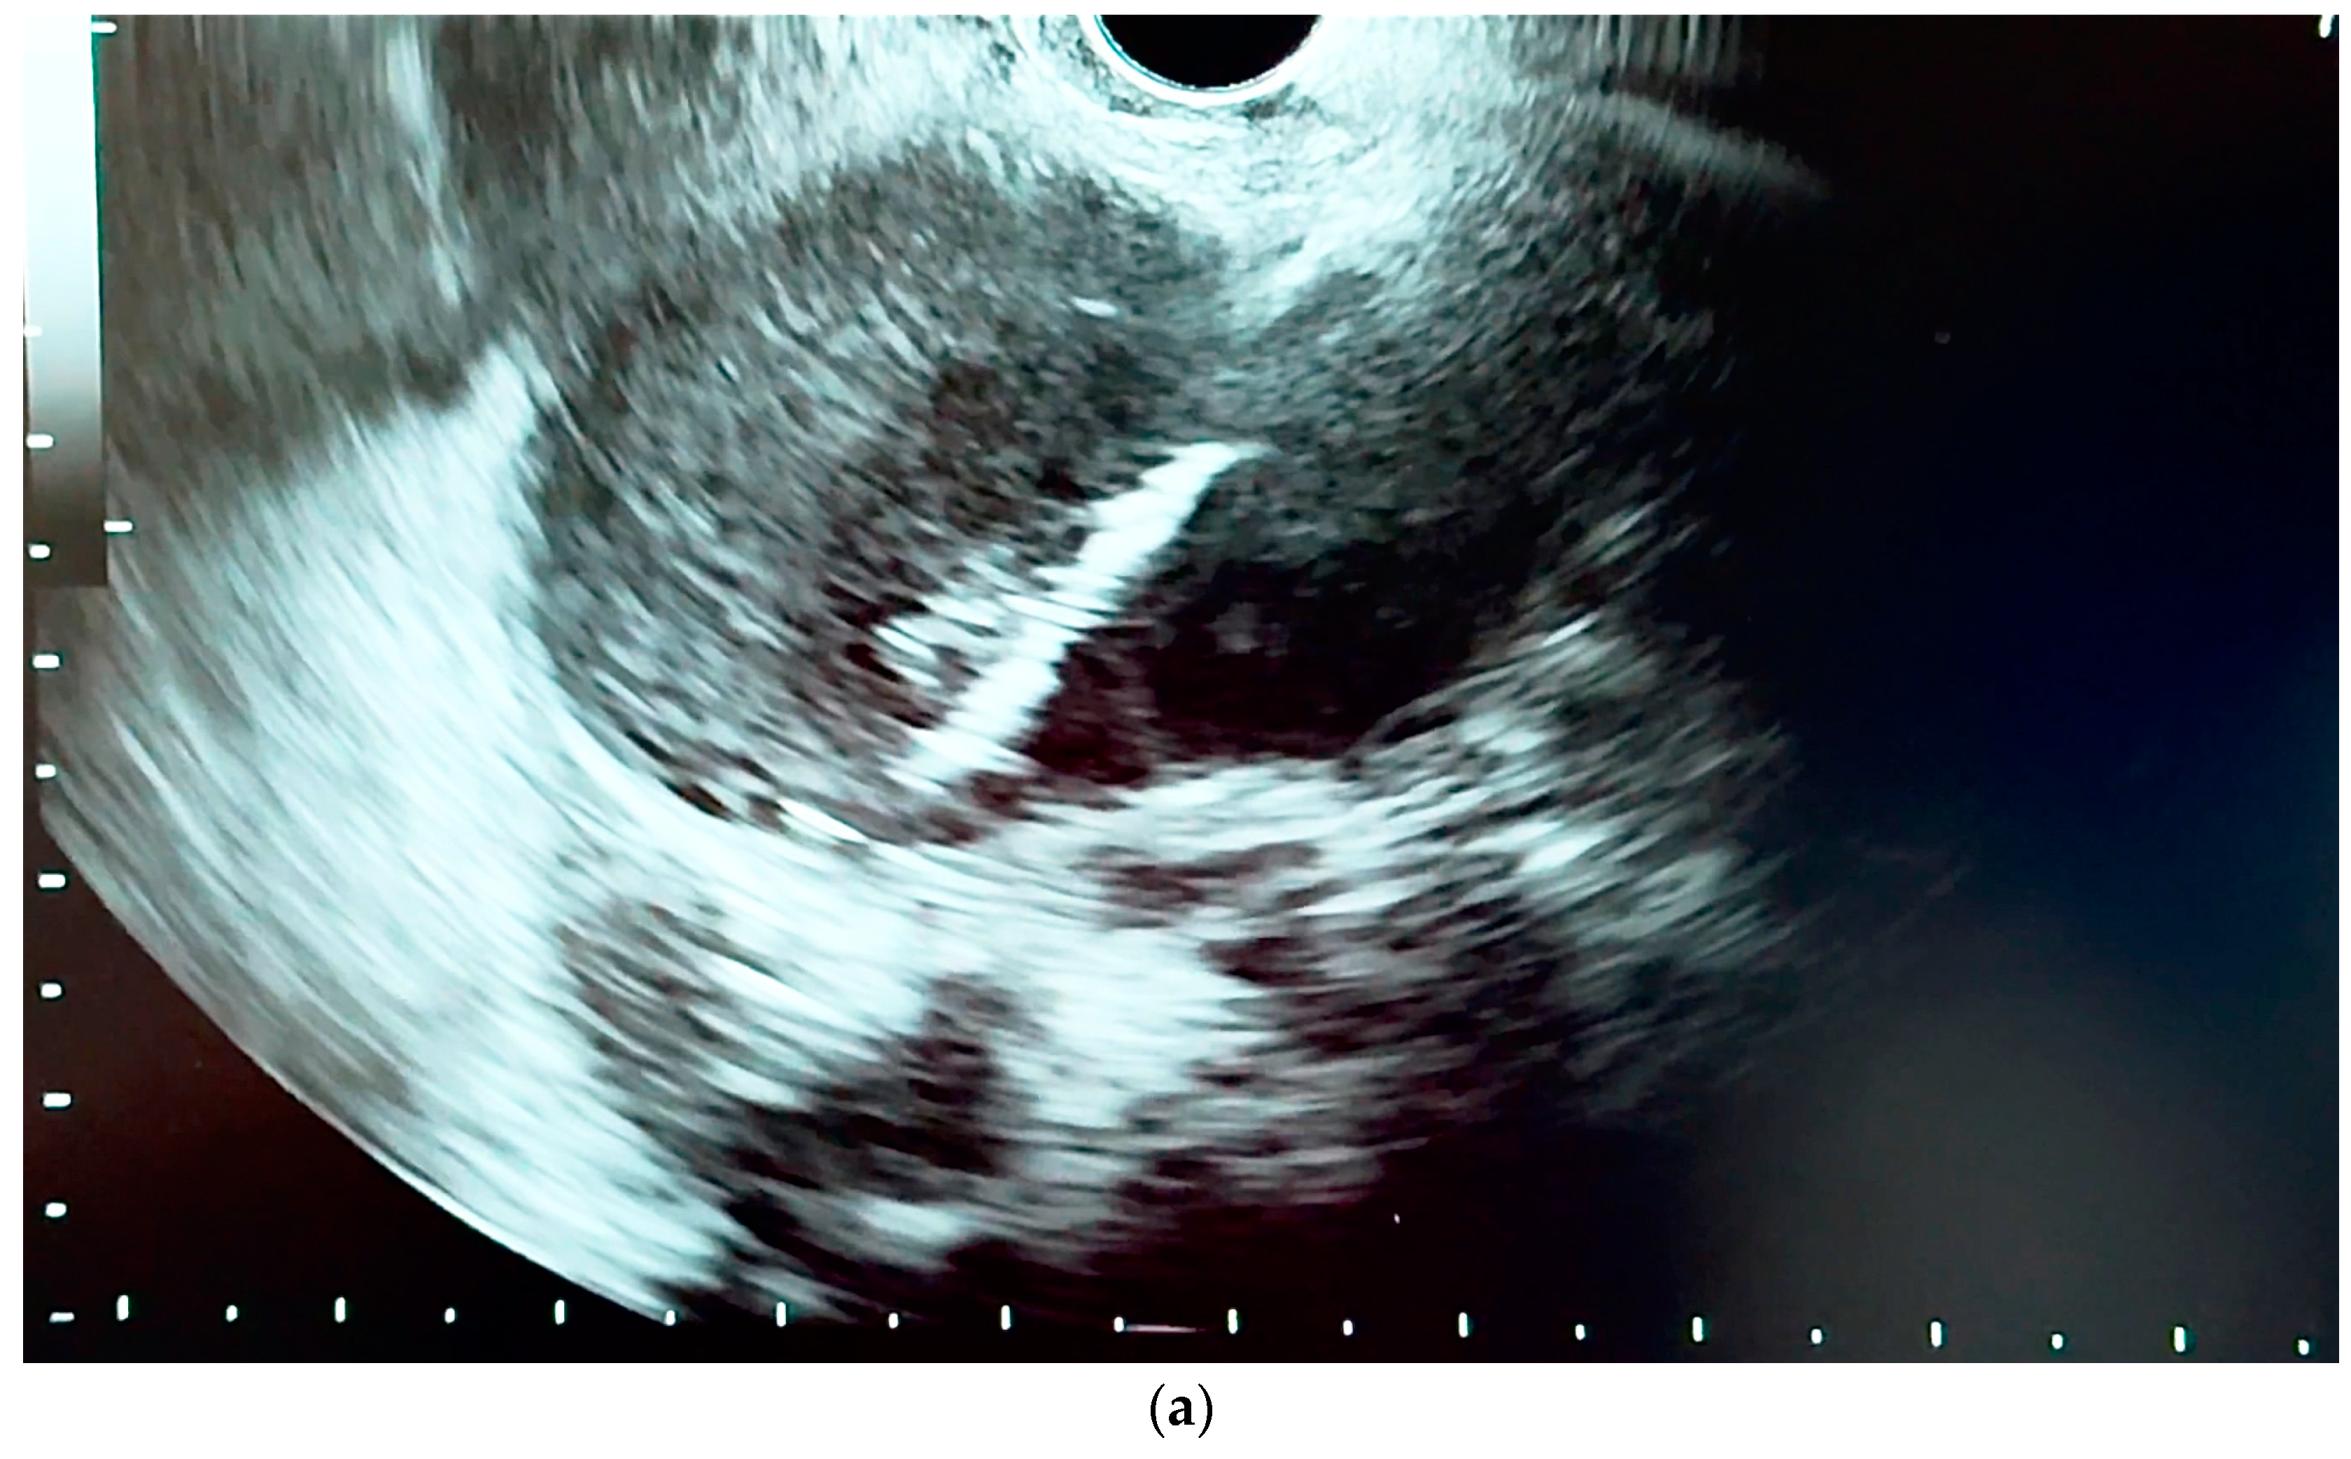

6.4.1. Endoscopic Ultrasound (EUS)

- Orzan, R.I.; Pojoga, C.; Agoston, R.; Seicean, R.; Seicean, A. Endoscopic Ultrasound in the Diagnosis of Extrahepatic Cholangiocarcinoma: What Do We Know in 2023? Diagnostics 2023, 13, 1023. [Google Scholar] [CrossRef] [PubMed]